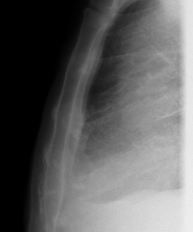

- RX Tórax

Técnica mediante la cual, utilizando rayos X, se obtienen imágenes de la caja torácica (corazón, pulmones, arcos costales, clavículas, etc.) para su estudio. - RX Esternón

Técnica mediante la cual, utilizando rayos X, se obtienen imágenes de los senos paranasales para su estudio. Indicaciones: cefalea, tos crónica. - RX Tórax

Una radiografía de tórax es una técnica mediante la cual, utilizando una pequeña dosis de radiación, se obtiene una imagen bidimensional de la caja torácica y su contenido (pulmones, corazón, mediastino, etc.). Es una de las pruebas médicas más comúnmente realizadas. - RX Abdomen